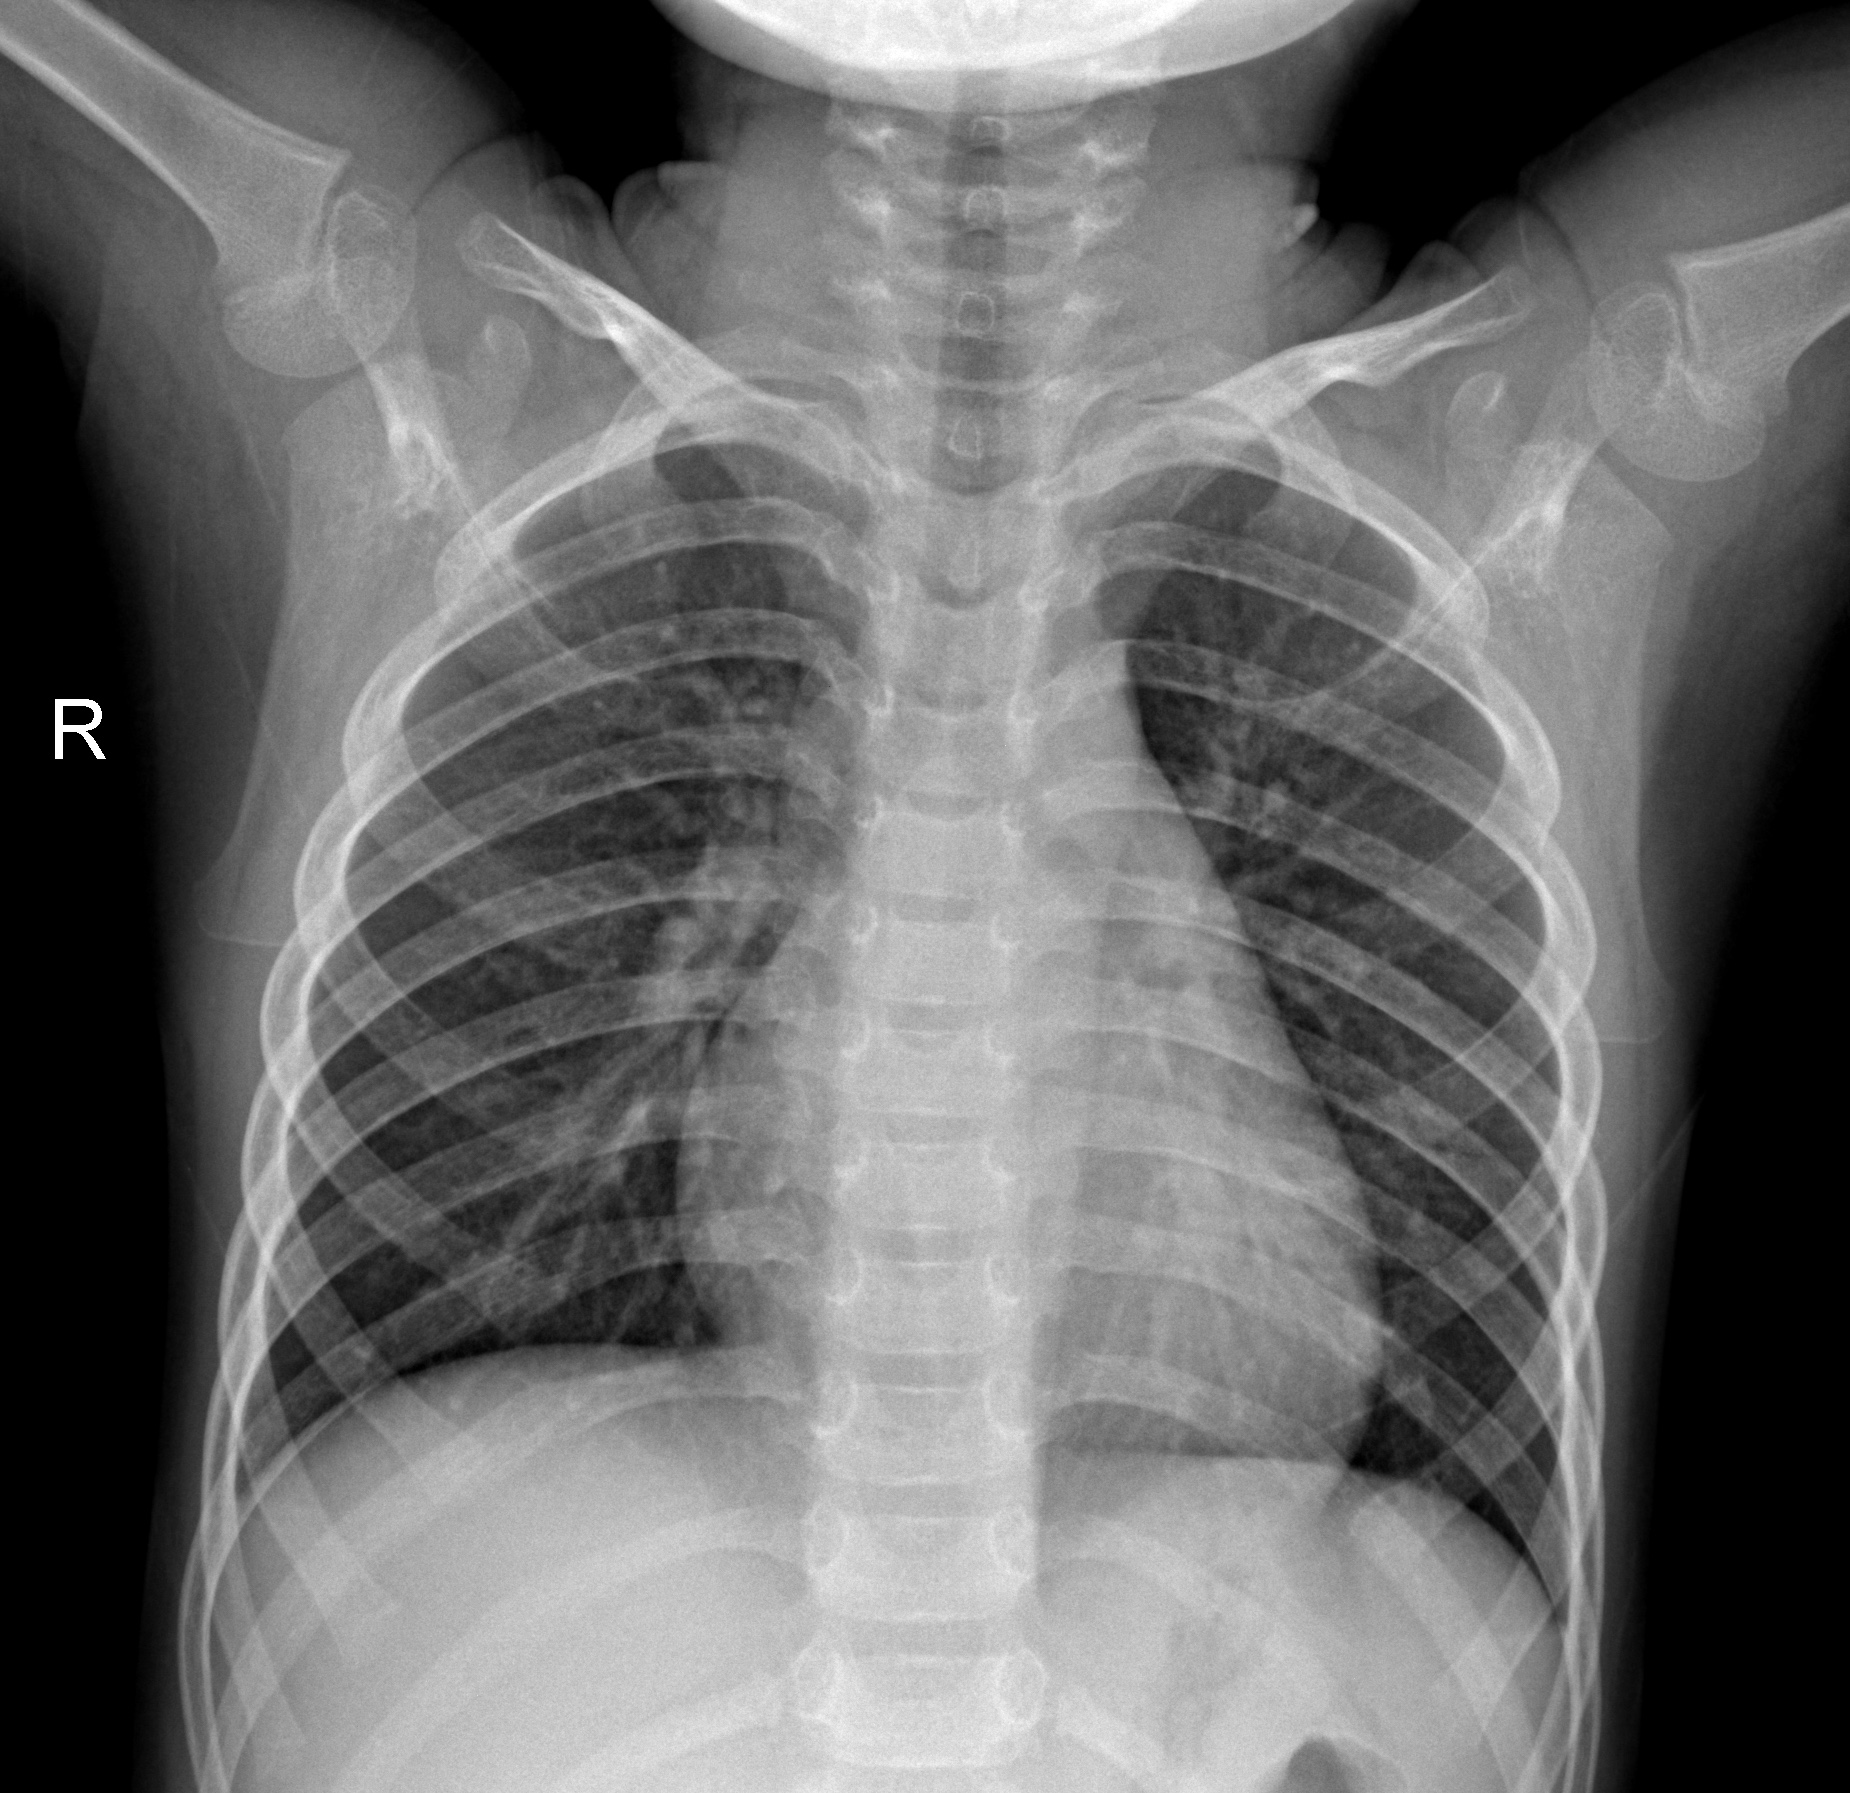

Pneumonia

Pneumonia